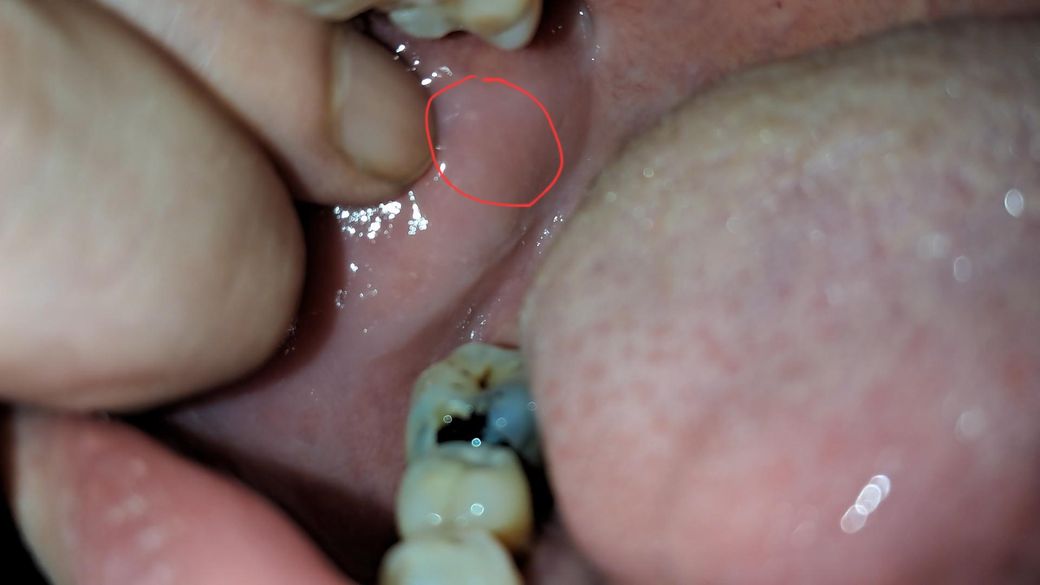

흰색점 구강암 증상인자 봐주세요 볼안쪽

작고 희미해서 잘 안 찍히네요

통증 출혈 궤양 없고요 촉감은 주위 살들이랑 같아요 튀어나온 것도 없고 오래 된 것 같은데 우연이 발견 했어요

그냥 나둬도 무해 한건지오

• 1번 째 사진

사진상에서는 특별히 문제가 보이지는 않는 것 같습니다. 너무 걱정하지 않으셔도 됩니다.

볼살이 치아에 계속해서 자극을 받아서 생긴 자국같습니다. 큰 문제가 잇는건 아니니 너무 걱정하지마세요.

사진으로 봤을 경우에는 구강암으로 보이진 않습니다. 너무 걱정하지 않으셔도 될 것으로 생각됩니다

자세한 확인을 위해서 치과에서 진료를 받아보는 것을 권유드립니다.